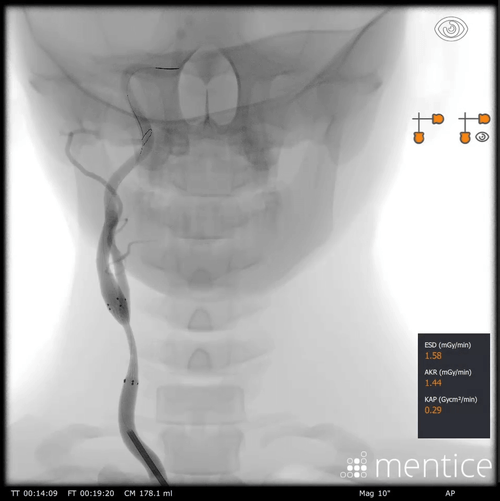

Our anatomical software physics engine, combined with haptic-enabled hardware solutions, creates the optimal environment for procedural adoption, proficiency-based training, patient-specific simulation, and objective skills assessment. Over 350 development years of engineering have created the most advanced IGIT simulation solutions on the market.

Over 2000+ systems delivered worldwide that cover fluoro & echo based learning solutions from head to toe for both Healthcare Professionals and the MedTech Industry.